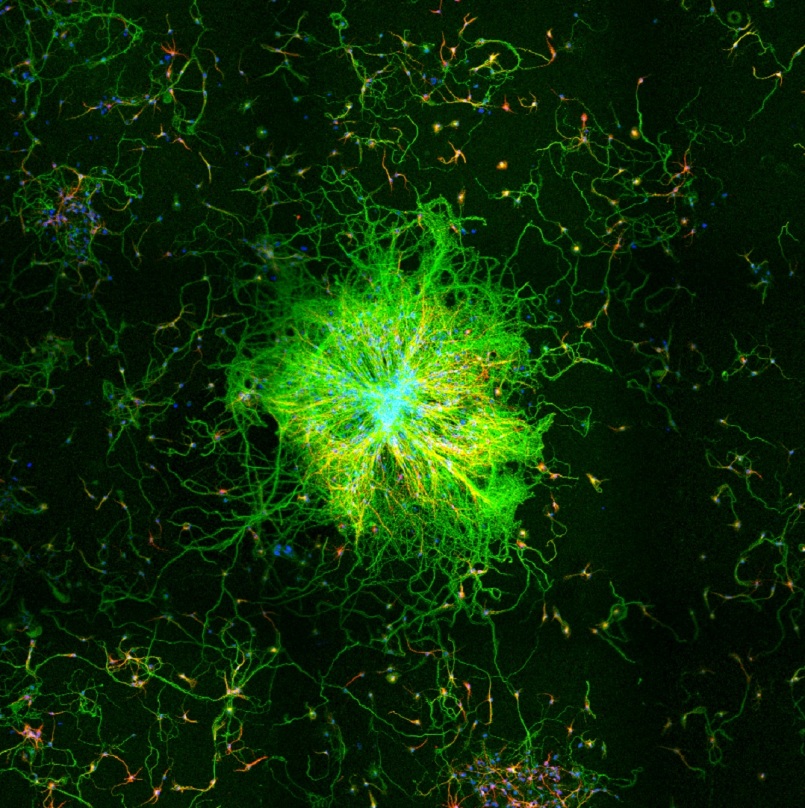

Neuroimmunology, neuroinflammation, and gut microbiota-immune-brain axis.

Approaches

1. Tuz A, Ghosh S, Karsch L, Antler M, Lakovic V, Lohmann S, Lehmann A, Beer A, Nagel D, Jung M, Hörenbaum N, Kaygusuz V, Qefalia A, Alshaar B, Amookazemi N, Bolsega S, Basic M, Siveke J, Heiles S, Grüneboom A, Lueong S, Herz J, Sickmann A, Hagemann N, Hasenberg A, Hermann D, Gunzer M, Singh V. Gut microbiota deficiency reduces neutrophil activation and is protective after ischemic stroke. J Neuroinflammation 2025 May. With DFG funding.

2. Tuz A, Hoerenbaum N, Ulusoy Ö, Ahmadi A, Gerlach A, Beer A, Kraus A, Hasenberg A, Hagemann N, Hermann D, Gunzer M, Singh V. Hypercholesterolemia triggers innate immune dysbalance and transforms brain infarcts after ischemic stroke. Frontier Immunology, 2025 Jan. With DFG funding

1. Nils Hörenbaum, University Duisburg-Essen (M.Sc. 2025), “Impact of high-fat diet on neutrophil activation and brain infarcts within three hours after ischemic stroke”.

2. Medina Antler, Heinrich-Heine-University, Düsseldorf ((M.Sc. 2024), “To understand the contribution of microbiota-dependent neutrophil activation on stroke outcome using germfree and antibiotic-treated mouse models“.

3. Vivian Lakovic, Heinrich-Heine-University, Düsseldorf (M.Sc. 2024), “To investigate the impact of intestinal microbiota on neutrophil activation and brain microvascular thrombus

formation using mass spectroscopy and light-sheet fluorescence microscopy“.